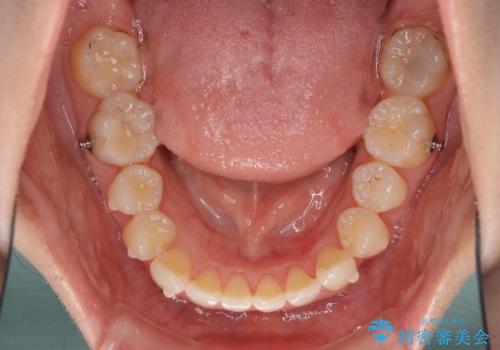

- 口元の深い咬み合わせ(ディープバイト)を気にして来院された患者様です。

インビザラインによる上下歯列の遠心移動(後方移動)により、口元のデコボコとディープバイトを改善することとしました。

下顎左右の犬歯とその後ろにある第一小臼歯、計4歯がシミュレーション通りに動かずディープバイトがなかなか改善されませんでした。

マウスピースの再製作を何度か行いましたがうまくいかないため、部分的にワイヤー矯正を併用することを提案しました。しかし、最も気になっていた前歯のデコボコはきれいに改善されたため、これ以上治療を希望されず、治療を終了することとしました。(今後気になった際には再開する予定です)